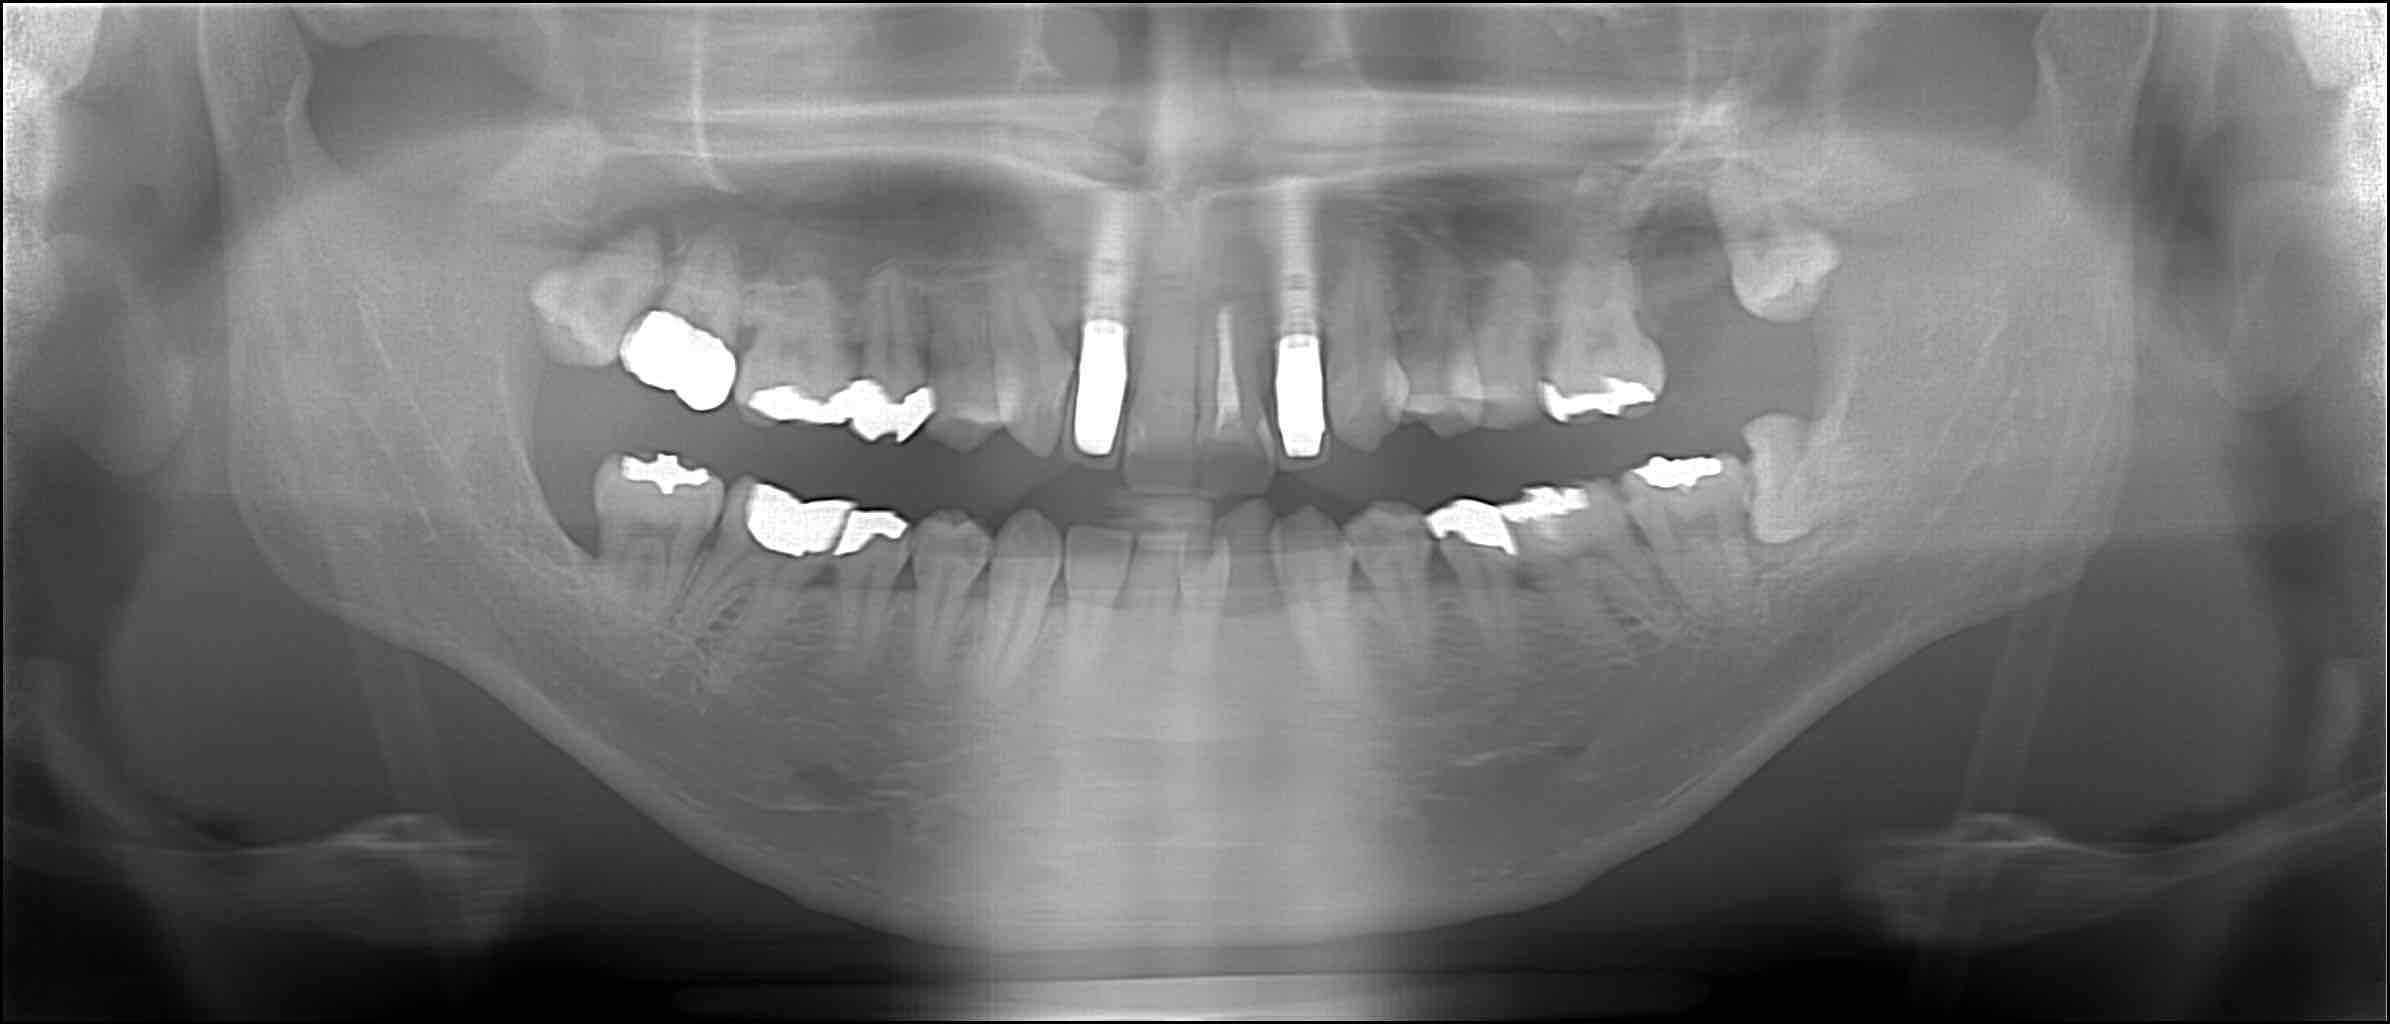

| インプラント | 25歳 男性 |

|---|---|

| 主訴 |

コンタクトスポーツにより、上顎の左右側切歯に動揺があり、咬合時に痛みがある。 |

| 治療内容 |

インプラント埋入(上顎左右側切歯、2本) 【上顎右側側切歯】 歯根嚢胞と遠心に骨欠損が認められた。患者様の希望により、インプラント治療を行うことになった。 インプラント埋入時に、下顎の親知らず側方より骨を採取して骨移植を行った。 【上顎左側側切歯】 インプラント埋入 |

| 治療結果 |

骨移植によって機能性と審美性に優れたインプラント治療ができました。 メンテナンスに継続して来院頂き、手術後10年以上経過していますが、インプラントの状態は良好です。 |

| 治療期間 | 7ヶ月 |

| 治療費用 | 126万円(税込) |

| リスク | 術後の痛み、腫れ。 |

手術前

手術後

10年後

術後10年が経過していますが、インプラントの状態は良好です。